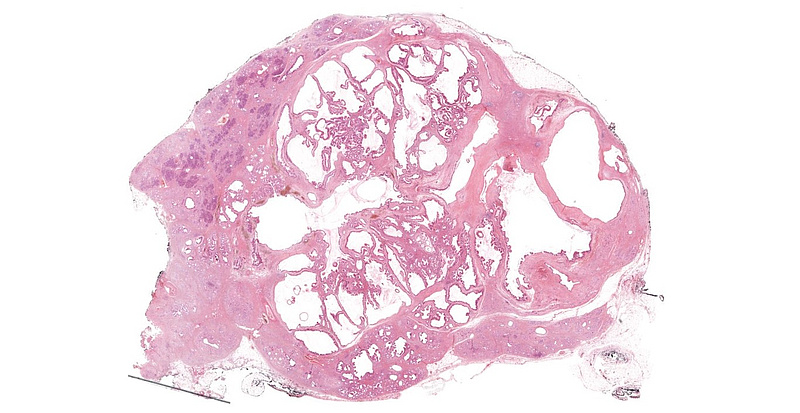

Immunohistochemistry demonstrated diffuse positivity for MUC5AC (Panel D). MUC6 was focally positive within the oncocytic component of the tumour (Panel E). Of note, intra- and interlobular fibrosis with remarkable atrophy of the acini was detected in the non-neoplastic area of the pancreas, mimicking well-differentiated (tubular) invasive carcinoma (Panel F). Endocrine cells were comparatively spared and the lobocentric architecture was preserved.